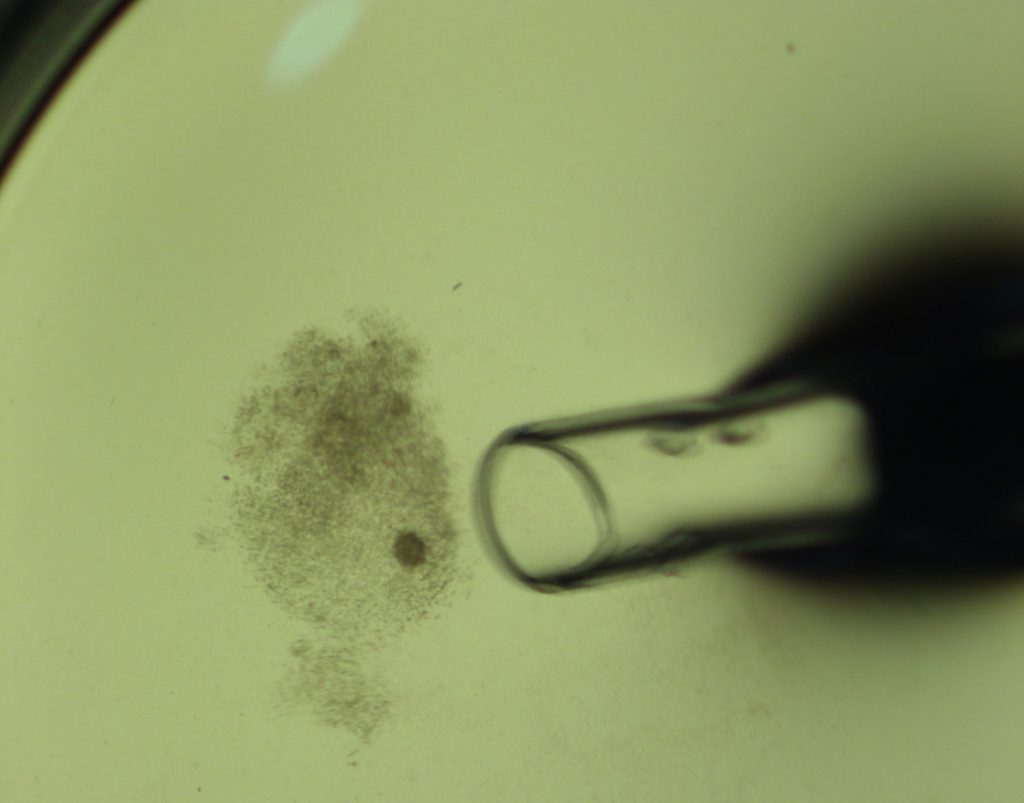

裸化処理でこのように少しずつ卵丘細胞を剥離していくのですが、、、

もう少し卵丘細胞を取り除きます、、、

綺麗なつるんとした卵子になっても、この倍率では成熟具合がわからないため、顕微鏡下で拡大して確認を行います。